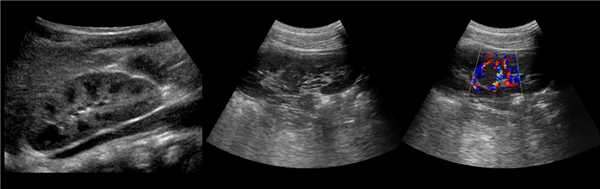

Клинический пример из второй группы. Пациент К. перенес операцию пересадки почки от живого родственного донора. Трансплантат в левой подвздошной области. Индекс резистентности в междольковых артериях составил 0,70 (рис. 5). В сегментарных артериях индекс резистентности составил 0,66 (рис. 6). Показатели жесткости паренхимы почечного трансплантата при режиме УЭСВ составили от 31,6 до 36,9 кПа (рис. 7-9).

Рисунок 5. Исследование у пациента К. в режиме цветовой и спектральной допплерографии. Индекс резистентности в междольковых артериях почечного трансплантата составил 0,70

Рисунок 6. Эхограмма пациента К. Кровоток в сегментарных артериях неизменен